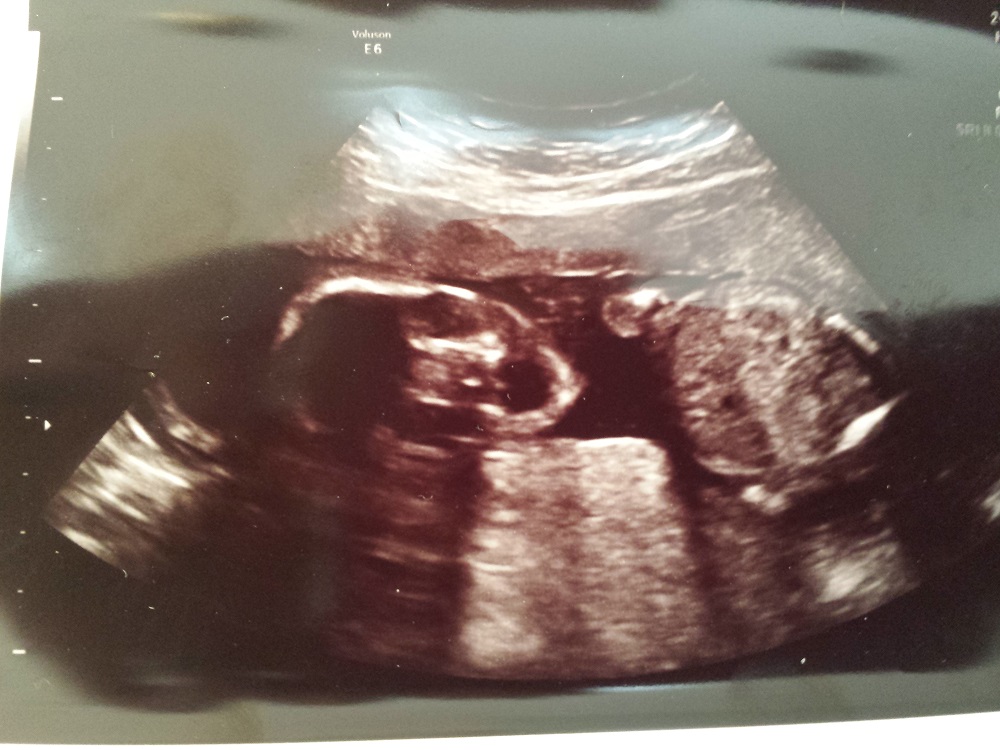

Anatomy ultrasound at 18 weeks 3 days

Attachment 12821